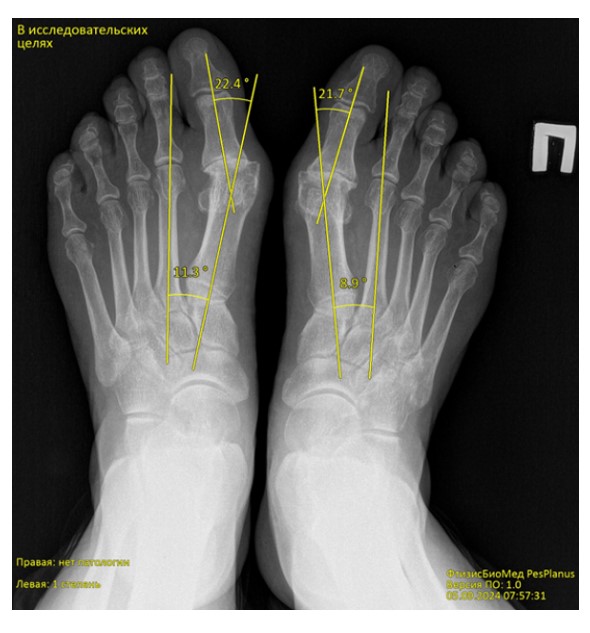

Chương trình phân tích tự động ảnh ‘X-quang bàn chân’ phát hiện bàn chân bẹt dọc và bẹt ngang

FtizisBioMed PesPlanus được phát triển nhằm phân tích tự động hình ảnh X-quang kỹ thuật số của bàn chân, hỗ trợ bác sĩ trong việc:

Phát hiện sớm các dấu hiệu bàn chân bẹt dọc và bẹt ngang;

Giải pháp công nghệ

Chương trình ứng dụng trí tuệ nhân tạo y tế (Medical AI) và các mô hình học máy tiên tiến để phân tích hình ảnh X-quang bàn chân. Hệ thống được huấn luyện trên tập dữ liệu lớn đã được gán nhãn bởi các chuyên gia đầu ngành, đảm bảo độ tin cậy và khả năng tái lập kết quả cao.